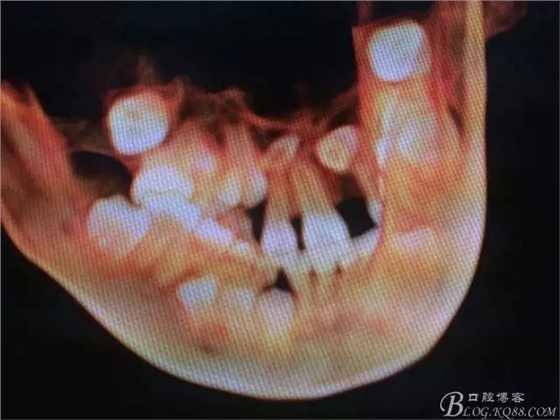

圖2.術(shù)前的CBCT的三維影像重建:多生牙的位置